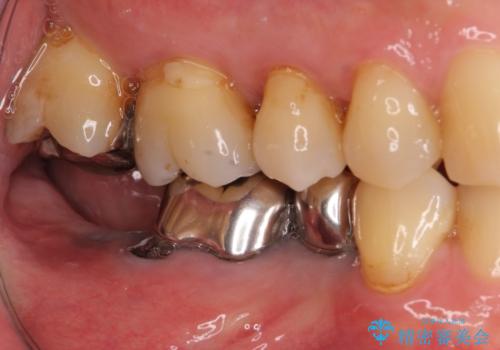

- 奥歯の欠損部へのインプラント治療を希望して来院された患者様です。

抜歯をしてから長年経過しており、レントゲンからは十分に骨があることが分かっていたため、速やかに治療を開始することとしました。

インプラント治療に当たり、手前の銀歯2本の審美回復も希望されたため、3歯のオールセラミッククラウンによる補綴治療を行うこととしました。

通常、奥歯を抜歯した状態で長年放置すると、咬み合う歯が伸びてきて、咬み合わせが乱れてしまうことが多いです。そのような場合には、部分的な矯正治療などが必要となるのですが、こちらの患者様は幸運なことに咬み合わせが乱れていなかったため、インプラント埋入から速やかに補綴治療を行うことができました。